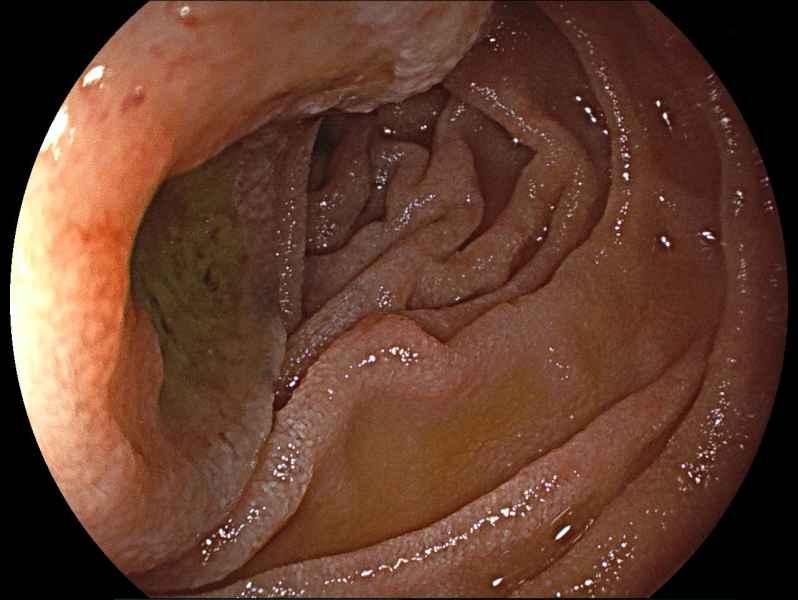

Atoll islands in a blue sea